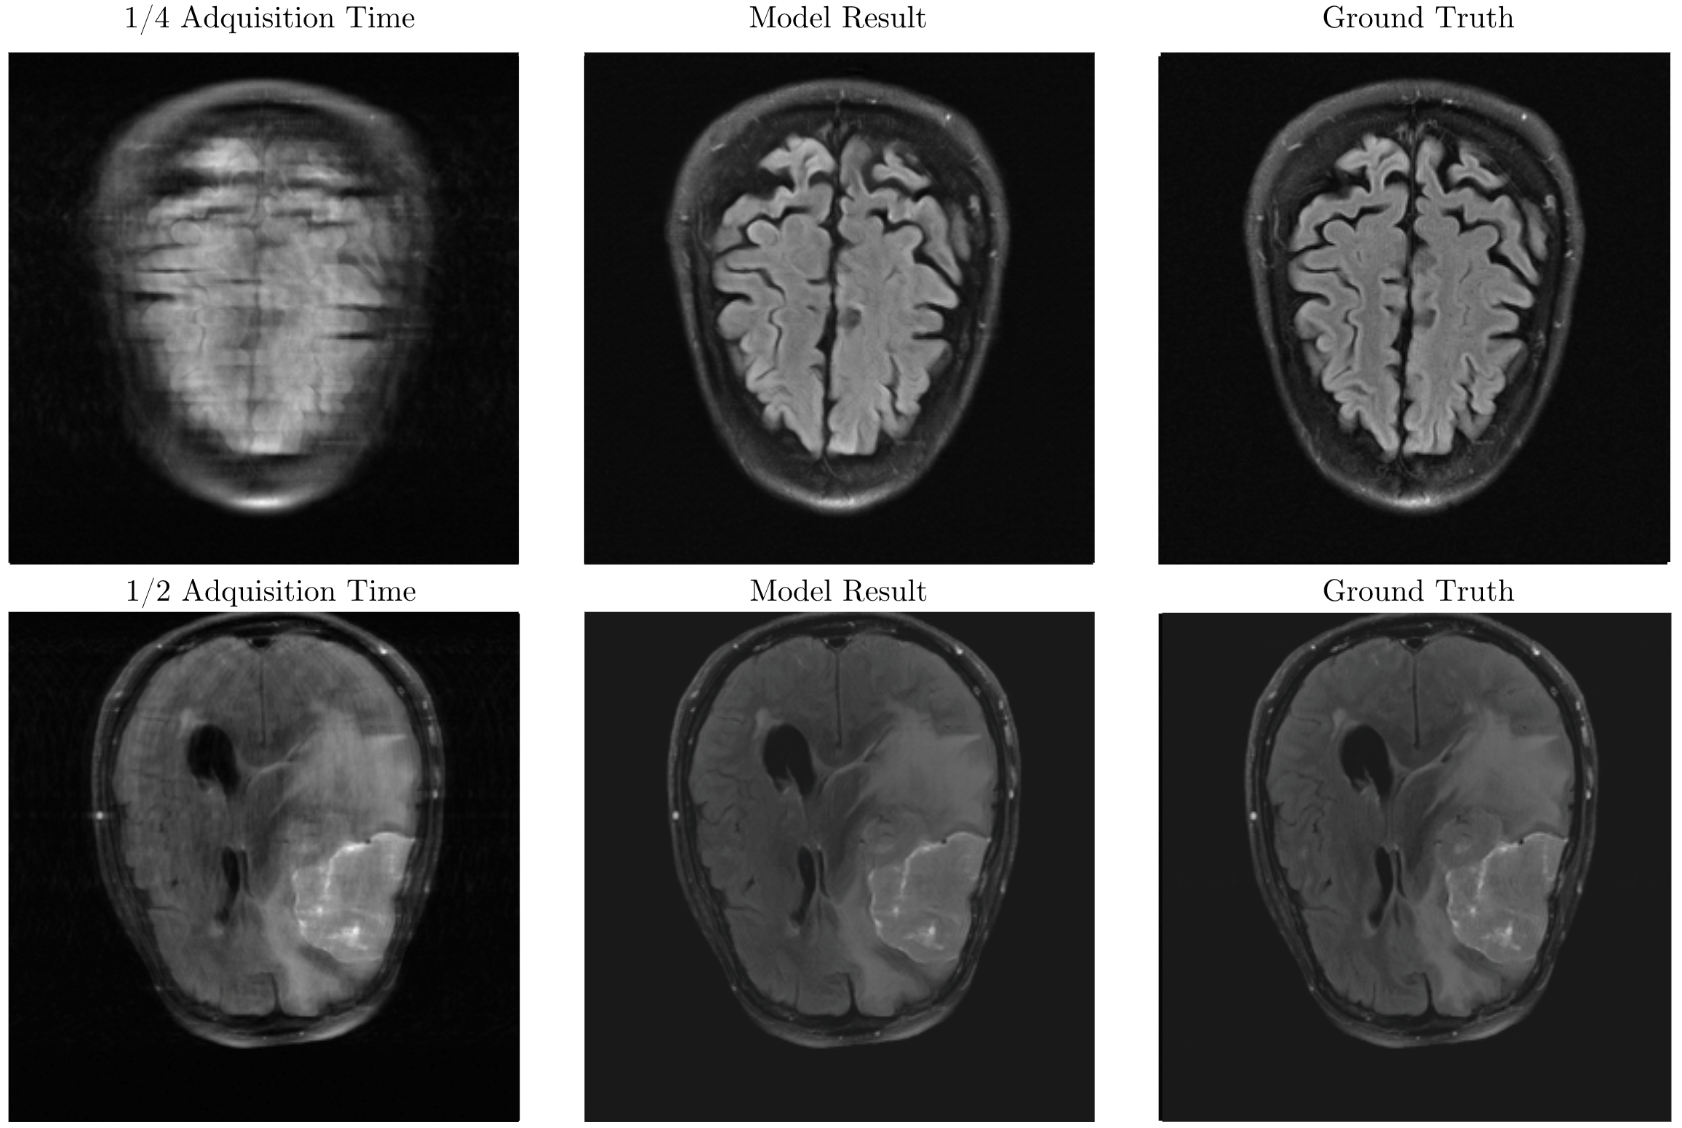

Scattnet-MR is a machine learning framework for accelerated MRI reconstruction that integrates wavelet scattering transforms with neural implicit representations to achieve robust and interpretable reconstructions.

The project focuses on combining physically grounded feature extraction with deep learning models to improve stability under noise and distribution shifts, addressing key limitations of black-box approaches in medical imaging.